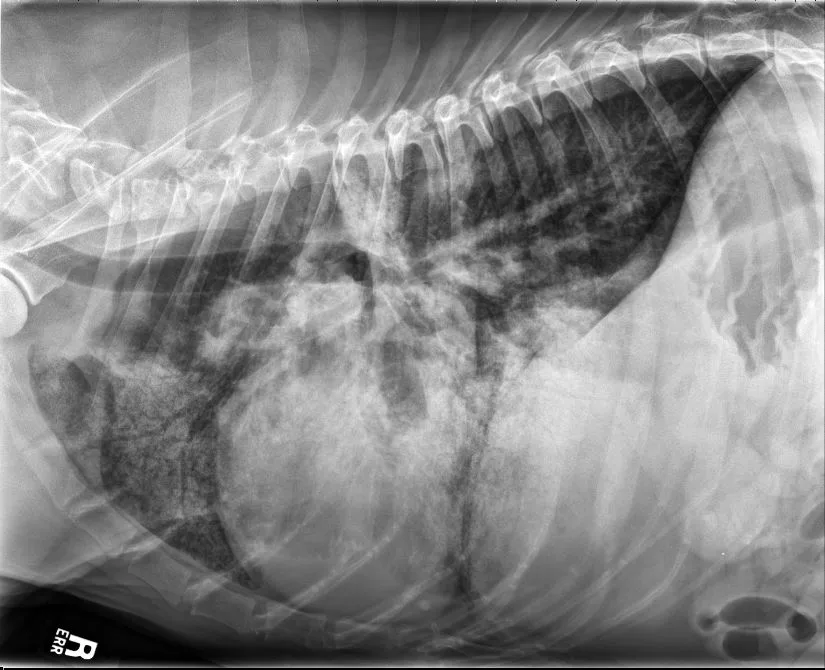

A subset of patients with acquired heart disease may develop left-sided congestive heart failure (CHF). In addition to left-sided cardiomegaly, dogs with active CHF secondary to MMVD commonly exhibit lobar pulmonary venous enlargement on radiographs, as well as an interstitial to alveolar radiographic lung pattern that typically develops in the perihilar region and right caudal lung lobes (Figure 8); however, in dogs with DCM, this lung pattern may be seen in the ventral lung lobes (Figure 9). The radiology lung score is an objective method to quantify severity but was not associated with the recurrence of CHF or survival in one study.16 Dogs administered diuretics may not have pulmonary venous dilation, and some dogs with CHF secondary to acute increase in left atrial pressure (eg, aortic valve endocarditis, chordae tendineae rupture) may not have significant cardiomegaly.

FIGURE 9 DV (left) and right lateral (right) projections consistent with left-sided CHF in a dog with advanced DCM. Perihilar to ventral distribution of the severe interstitial to alveolar pulmonary pattern is present in addition to cardiomegaly. VHS, VLAS, M-VLAS, and VRHi collected from the right lateral view are 11.5, 2.1, 4.1, and 3.1, respectively. (Note: The DV image is flipped to display the right side of the patient to the left.)